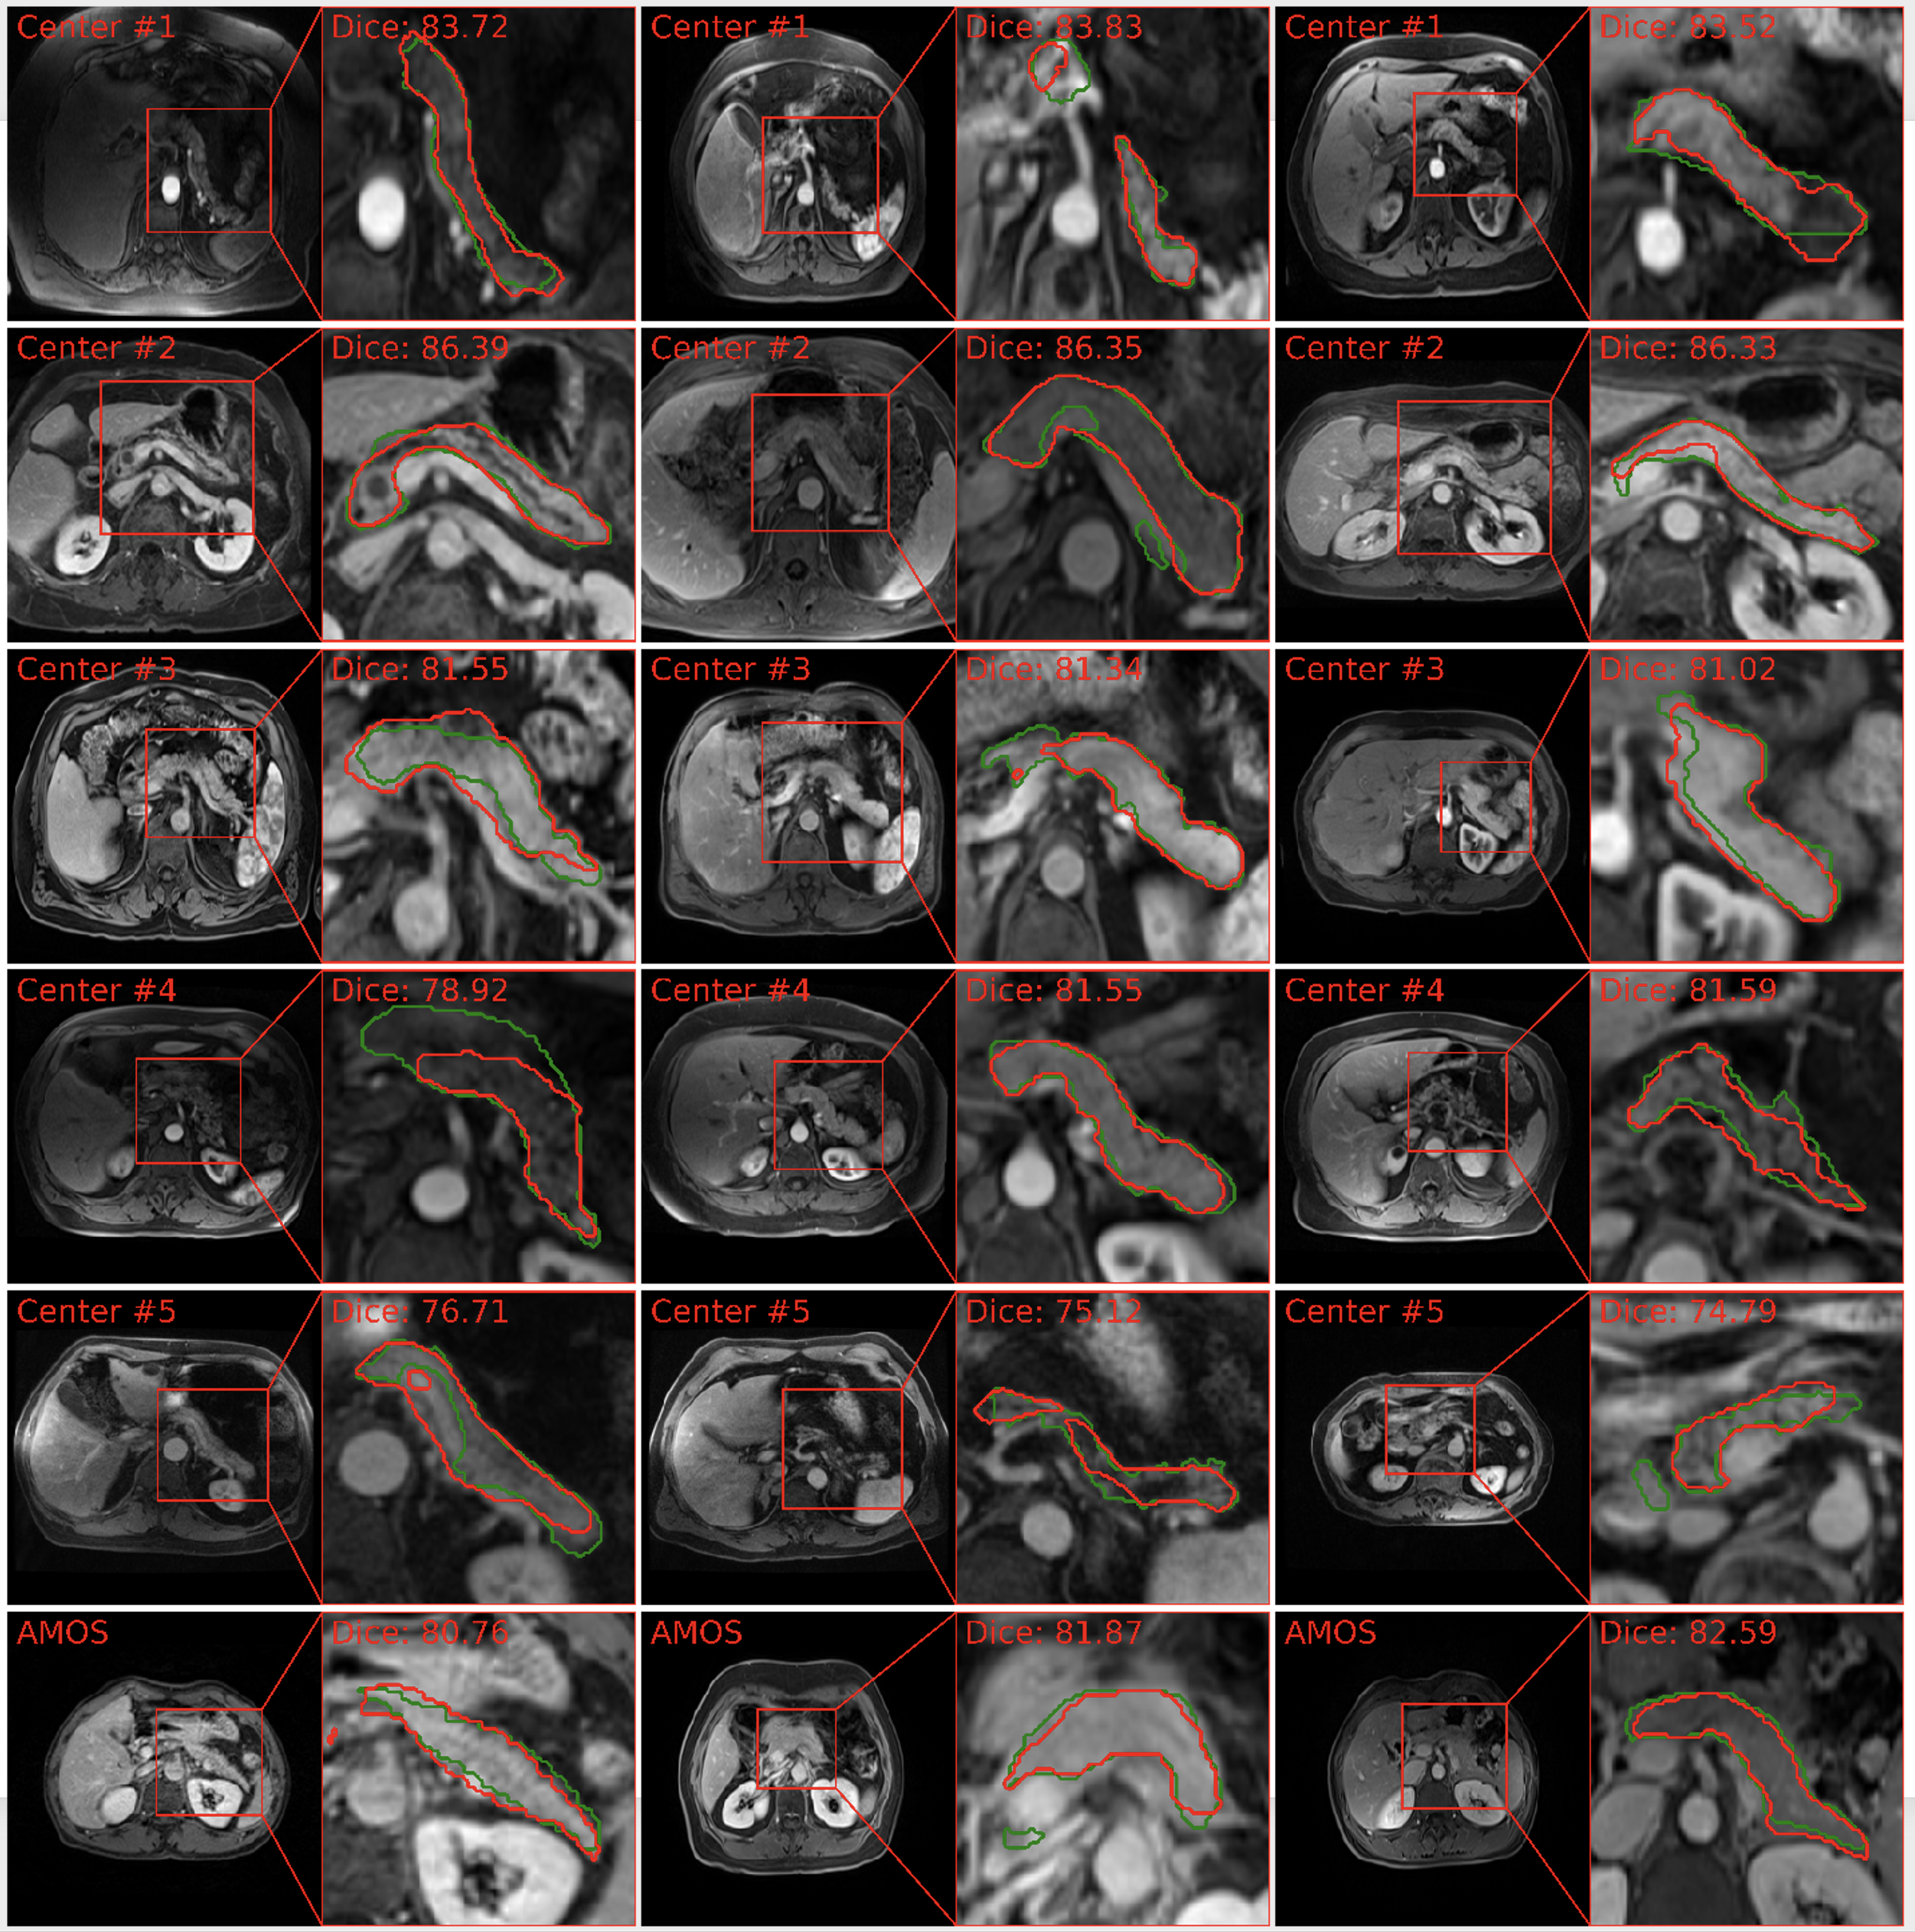

4.3.2 T2W MRI

Our PanSegNet similarly demonstrated strong segmentation capabilities on T2W sequences. Within the source domain (Center#1 and Center#2 datasets), the model achieved an average Dice coefficient of 86.27% with a standard deviation of 6.44% (median: 87.84%). When assessing the segmentation performance in the Center#3 dataset, we observed a considerably high Dice coefficient of 87.83% (±1.80%, median 89.22%). When deploying the model in out-of-distribution settings (Center#3 and Center#5), the Dice coefficients were decreased to 81.41% (-5.63%, p-value: 4.23×10-4) and 83.03% (-3.76%, p-value: 1.79×10-2), respectively, implying the impact of domain shifts. Despite the shifts, the results are still at the forefront of current advancement. Visual results are illustrated in Figure 6, which closely aligned with ground truth annotations.

Refer to caption

Fig. 6: MRI T2W pancreas segmentation visualization across various data centers. The segmentation delineations illustrate the model’s capability to delineate pancreas boundaries precisely, exemplified by the accurate results. The Center #3 T2W segmentation also exhibits relatively high results, showcasing its segmentation potential. We observe domain shifts in external validation from Centers #3, #4, and #5.